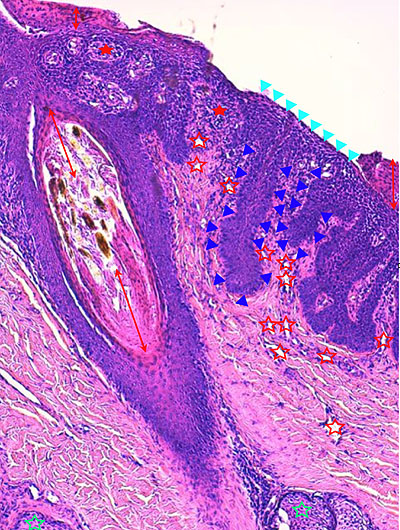

Photo 3 (Hémalun Eosine X 100) : aspect bleu-blanc-rouge à plus fort grossissement,

bleu pour hyperplasie des couches basales, blanc pour vacuolisation des acanthocytes

sous-cornés et rouge pour parakératose de la couche cornée. Le derme superficial est

le siège d’un infiltrat inflammatoire mononucléé périvasculaire modéré.

Légendes de la Photo 3 :

- Flèche bleue pour hyperplasie des couches basales

- Flèche blanche pour vacuolisation des acanthocytes sous-cornés

- Flèche rouge pour parakératose de la couche cornée

- Étoile rouge : Le derme est faiblement à modérément inflammatoire

Photo 4 (Hémalun Eosine X 100) : aspect bleu de l’épiderme pour hyperplasie des couches basales, qui dessinent des crêtes épithéliales allongées, filiformes, ramifiées et branchues, peuplées de cellules basales hyperbasophiles. L’épiderme est multifocalement exulcéré. L’infundibulum folliculaire visible présente une hyperkératose parakératosique sans visualisation nette d’une couche des grains. Le derme montre une discrète angiectasie des capillaires du plexus superficial ainsi qu’un discret infiltrat inflammatoire périvasculaire superficial.

Légendes de la Photo 4 :

- Triangles bleus foncés : contours de crêtes épithéliales allongées, filiformes, ramifiées et branchues, peuplées de cellules basales hyperbasophiles.

- Triangles bleus clairs : exulcération épidermique

- Flèche rouge : parakératose épidermique et folliculaire

- Étoile rouge pleine :Le derme est faiblement à modérément inflammatoire (infiltrat mononucléé)

- Étoile rouge creuse : angiectasie des capillaires sanguins

- Étoile bleue claire : glandes sébacées